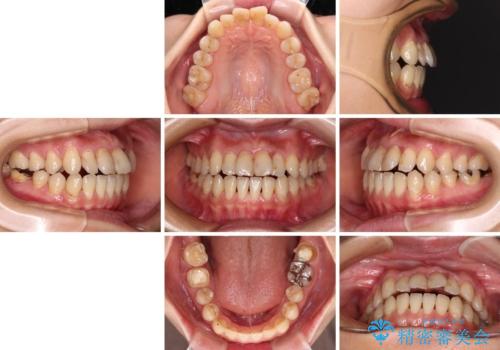

【モニター】開咬を治したい インビザラインによる矯正治療

- 20代女性

- インビザライン

- 2年3ヶ月

- 上下前歯の開咬とデコボコを気にして来院された患者様です。

開咬(オープンバイト)はインビザラインによる矯正治療がワイヤー装置と比べて圧倒的に有利であるため、インビザラインによる矯正治療を行うこととしました。

通院されなかった時期があって治療期間が長くなったり、奥歯に抜歯が必要な歯があったりと、治療は一筋縄にはいきませんでしたが、何とか治療を終えることができました。

今後はインプラント治療やむし歯治療を進めて行く予定です。